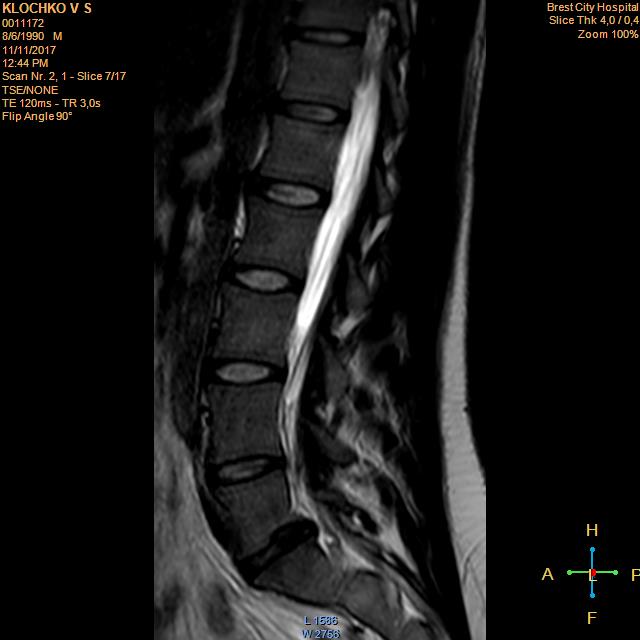

Тренировки с межпозвоночной грыжей.